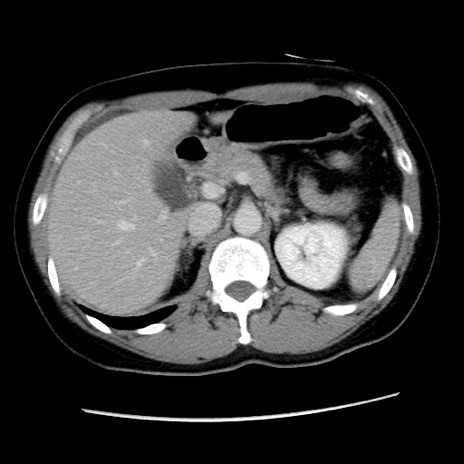

症例10(横断像)

【症例】 50歳代女性

【主訴】 腹痛

【現病歴】前日生レバーを食べた。今朝に排便あり。 昼前に突然発症の腹痛を生じ、当院救急外来を受診した。

【既往歴】 子宮筋腫にてで子宮全摘後

【身体所見】 意識清明、腹部:平坦、軟、下腹部やや左を中心に圧痛・反跳痛あり、筋性防御あり

【データ】WBC 7800、CRP 0.07